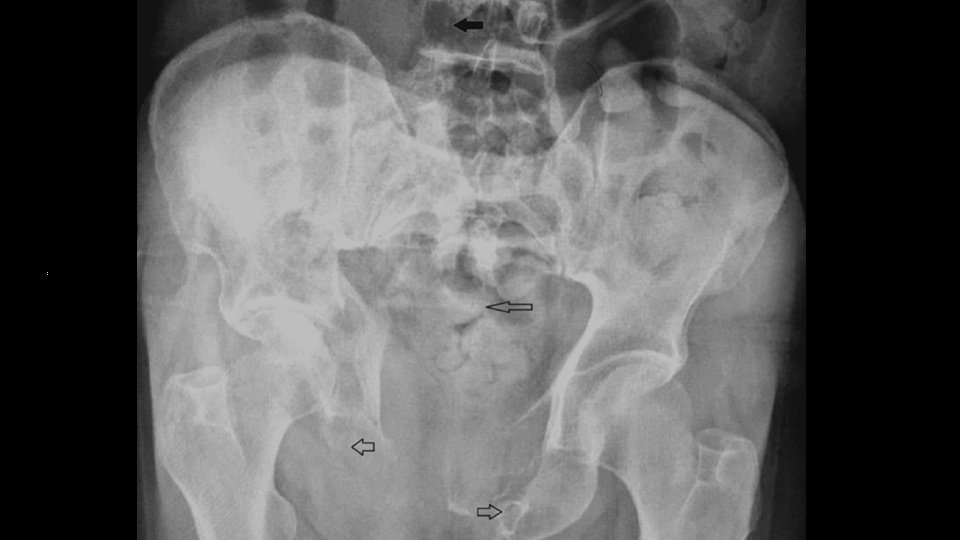

A sixty-seven-year-old male presented to the emergency department with a complaint of lower back pain for 4 months. There was no history of trauma. The pain was on and off, radiating to his right hip and gluteal region, worsening for the last two weeks, and associated with walking difficulty for the last ten days. Within this period, the patient was seen multiple times in primary health care services and at the ED. Detailed neurological examination was reported as normal. Non-steroidal anti-inflammatory drugs were prescribed at various times at the health center and ED, but the patient's complaints gradually increased, although there was no reduction in his pain during these four months. He had a past medical history of hypertension, chronic gastritis, and liver cirrhosis post hepatitis B, with no regular follow-up for the last three years. During the last ED visit, the patient’s vitals were stable. On physical assessment, motor and sensory examination results were normal. There was tenderness in the right gluteal region and the lower back. At the same time, it was seen that the anal sphincter tone was normal. There was no saddle anesthesia or signs of dropping foot. The X-ray of the pelvis and thoracic spine showed a compression fracture of thoracic (T) 9 vertebra, absence of right pedicle of lumbar (L) 4 vertebra, destruction of bilateral pubic rami and ischial tuberosity, a large pelvic bone lytic lesion accompanied by a secondary pathological fracture, as well as a large soft tissue component eroding the adjacent part of the sacrum (Figure 1).

Thoracolumbar spine and pelvis computed tomography (CT) performed and showed multiple lytic lesions in the thoracic and lumbar spine involving both vertebral bodies and posterior elements of the spine. Bilateral pelvic bones multifocal lytic lesions with pathological fractures are seen (Figure 2).